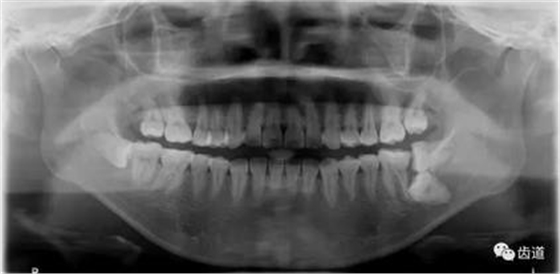

2、下頜磨牙阻生

下頜第二第三磨牙阻生口腔曲面斷層片影像

下頜第二第三磨牙阻生CBCT影像定位

三種圖片的影像學(xué)比較